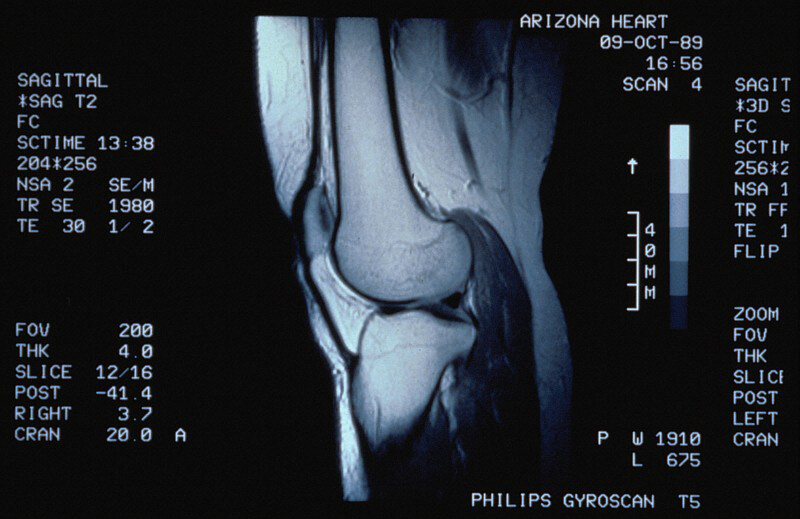

Врачи отмечают, что магнитно-резонансная томография колена является важным инструментом для диагностики различных заболеваний и травм. МРТ позволяет получить детализированные изображения мягких тканей, связок и хрящей, что особенно полезно при подозрении на повреждения менисков или связок. Специалисты рекомендуют проводить исследование в специализированных медицинских центрах, где есть современное оборудование и опытные радиологи. Важно, чтобы пациент заранее проконсультировался с врачом, который сможет направить его на МРТ и объяснить, как правильно подготовиться к процедуре. Врачи подчеркивают, что своевременная диагностика с помощью МРТ может значительно ускорить процесс лечения и восстановление после травм.

МРТ колена может помочь обнаружить такие проблемы, как повреждение связок и хрящей вокруг колена. МРТ также может выявить причину необъяснимой боли в колене, беспричинную неустойчивость колена или инфекции в колене или вокруг него.